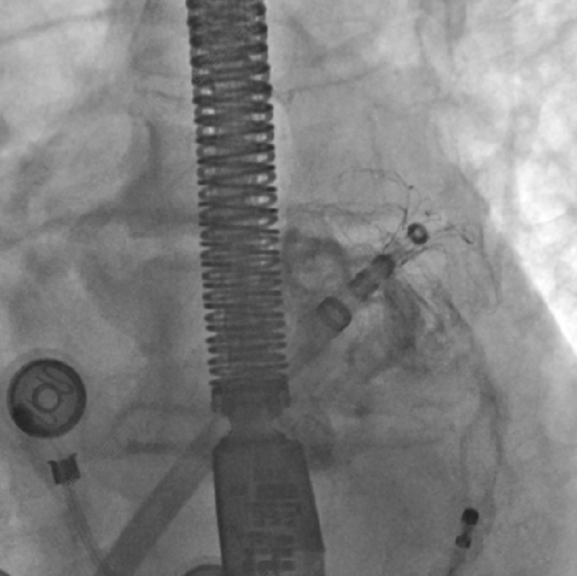

如图3所示,术中造影显示患者的左心耳固定区尺寸为23mm、深度25mm,选用规格为锚定盘直径26mm,密封盘直径 31 mm的左心耳消融封堵器植入到左心耳内。如图4-5所示,消融前后采用德诺电生理标测导管对左心耳进行电信号检测,对比结果表明左心耳电信号完全隔离;如图6所示,术者分别在左心耳消融前后进行了冠状动脉造影,造影显示回旋支无明显变化,无痉挛等不良事件发生;如图7-8所示,封堵器解脱前对左心耳消融封堵器进行了牵拉测试,器械无移位,造影及TEE超声显示左心耳完全封堵,无残余分流。

图3左心耳消融封堵器封堵至左心耳内